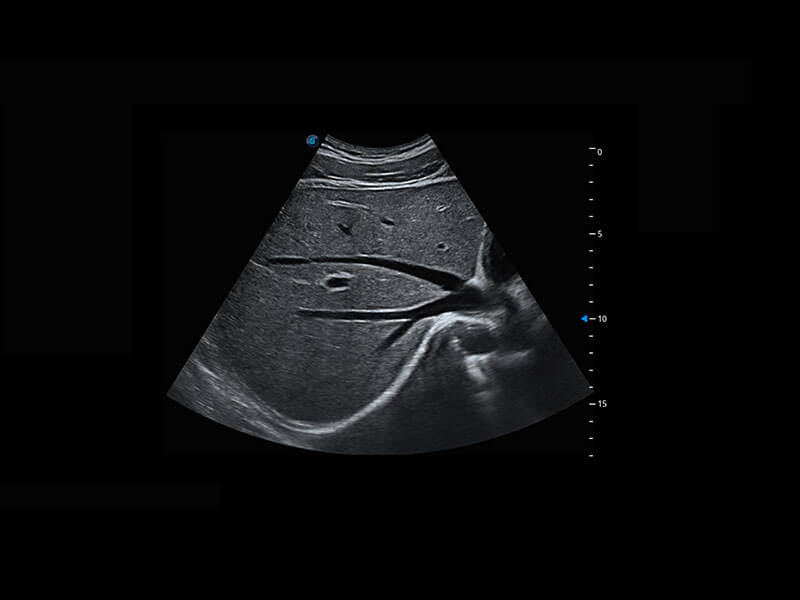

新生儿肝血管癌

新生儿脊髓圆锥